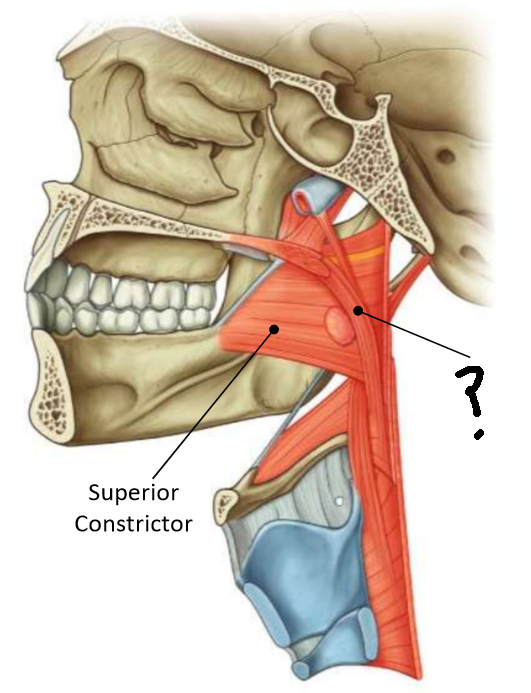

What muscle is this?

superior constrictor

What is the upper border of this muscle?

palatopharyngeal sphincter

What is 1?

pterygomandibular raphe

What is 2?

stylohyoid ligament

What are the attachments of this muscle?

pterygoid hamulus, pterygomandibular raphe, posterior end of mylohyoid line → pharyngeal raphe